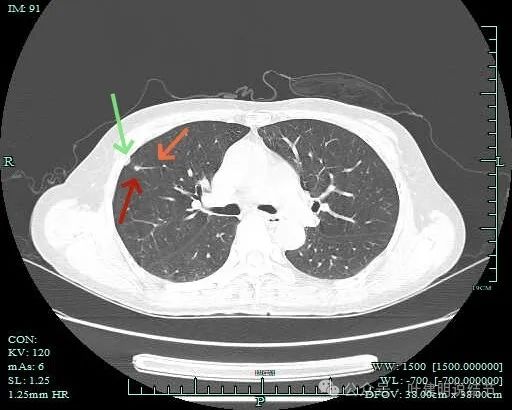

右上另有实性病灶,有血管进入且有异常增粗,相应胸膜有增厚。